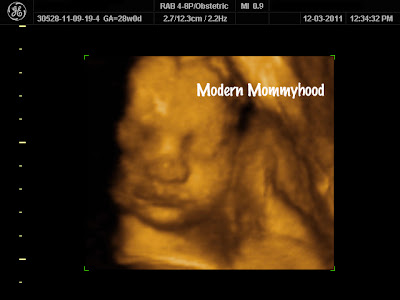

| Hubby is for sure she’s going to look like me because of the chin and nose. |